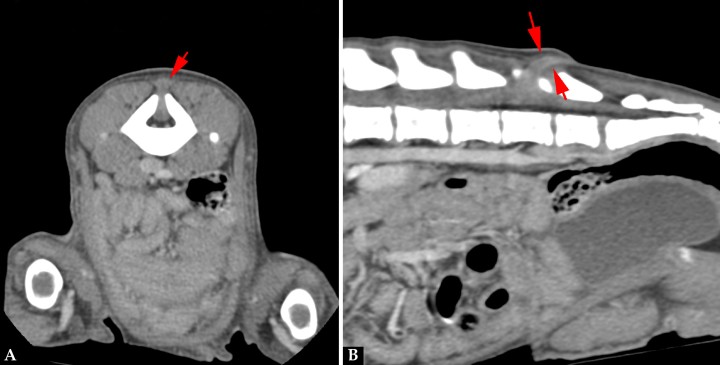

La mielografía podría ayudarnos a valorar el espacio subaracnoideo si sospechamos de un MC/MMC, aunque las técnicas de imagen avanzada, tomografía computarizada (TC) y resonancia magnética (RM) son las pruebas recomendadas si se sospecha de un defecto del tubo neural (DTN). Se realizó un estudio TC (General Electric Brivo CT385 Series de 16 cortes, Hangwei Medical Systems Co Ltd, Beijing, China, 16 cortes) sin y con contraste intravenoso, en el que se observó hipoplasia de la apófisis espinosa de L6 sin fusión de las láminas dorsales dejando un espacio abierto que comunicaba el canal vertebral y el tejido blando lumbar caudodorsal a L6 (Fig. 3). En las imágenes obtenidas en ventana de tejidos blandos tras administración de contraste se apreció el paso por el defecto espinal de tejido del canal vertebral con atenuación tejido blando y realce periférico, hasta el tejido blando dorsal a L6-7 (Fig. 4).

Imágenes de TC en ventana de tejidos blandos postcontraste. (A) Plano transversal. Defecto óseo vertebral con paso de tejido del canal vertebral, con atenuación tejido blando y realce periférico, hasta el tejido blando dorsal a L6-7 (flecha roja). (B) Reconstrucción en plano sagital.

Los hallazgos tomográficos indicaban la presencia de un DTN, espina bífida y MC/MMC. El diagnóstico diferencial incluiría un seno dermoide (SD) y el síndrome de médula anclada.